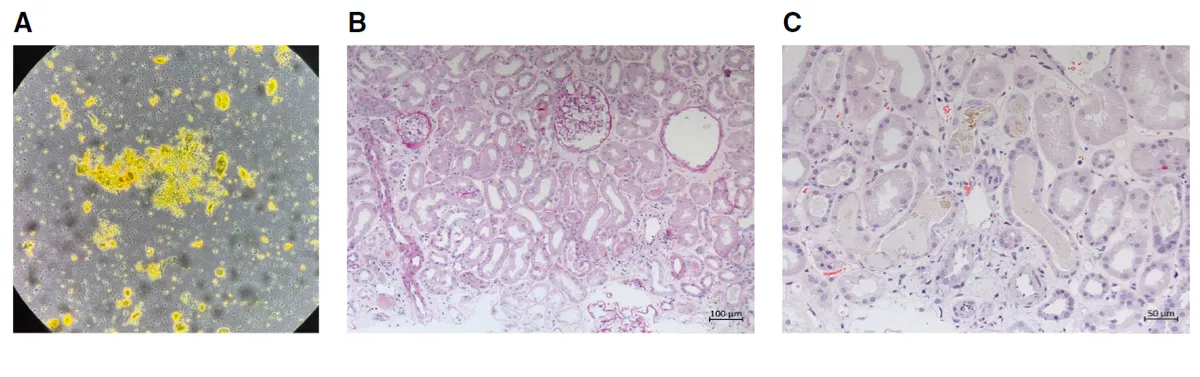

IRA + Icterícia: Um Caso que Exige Investigação Detalhada